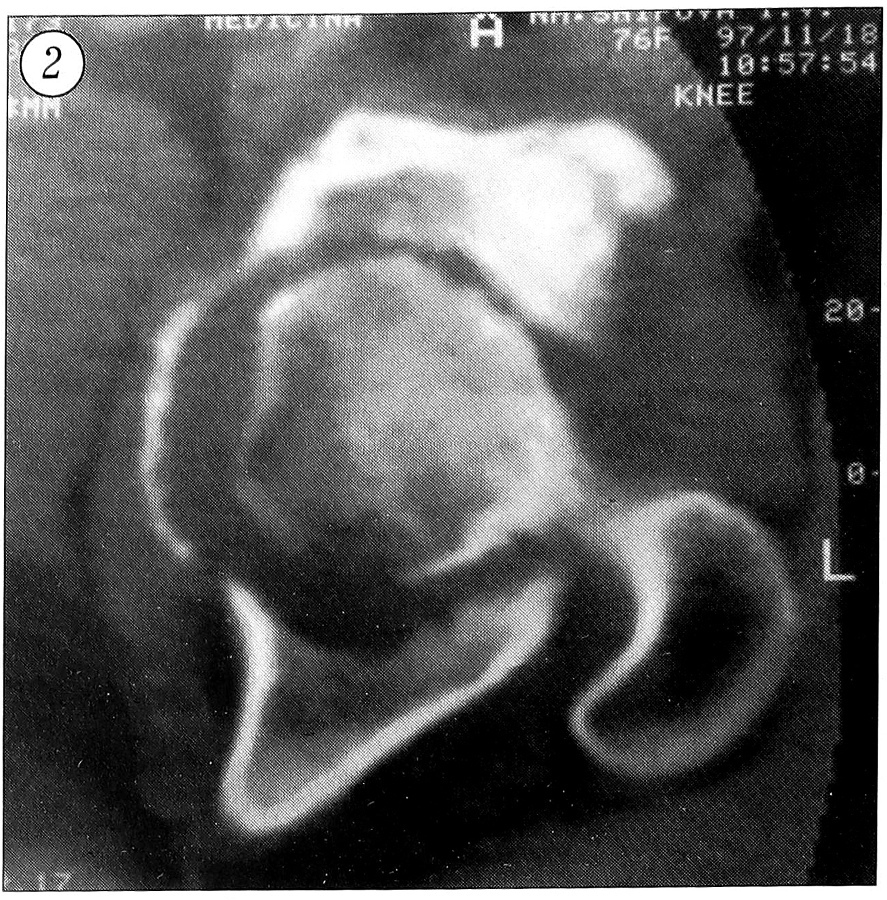

При прогрессировании процесса рентгенологическое обследование выявляет грубую деформацию вертлужной впадины, нарушение ее пространственной ориентации. Головка бедренной кости находится глубоко во впадине. Суставная щель резко сужена или отсутствует вследствие разрушения и дегенерации покровного хряща сочленяющихся поверхностей. Структура головки бедренной кости характеризуется склерозированием ее по сегментарному или тотальному типу. Со стороны краев вертлужной впадины формируются костно-хрящевые выросты треугольной формы, которые наподобие панциря покрывают шейку бедра, приближаясь к основанию большого вертела. Отчетливо определяется нижний край вертлужной впадины, который окружает головку бедра снизу, переходя на шейку (рис. 1).

Рис. 1. Рентгенограмма правого тазобедренного сустава больного с посттравматической протрузией вертлужной впадины.